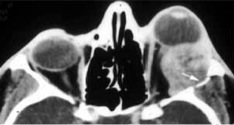

Computed tomography (CT) and magnetic resonance imaging (MRI) may demonstrate an ovoid soft tissue mass in the superotemporal orbit with irregular margins and possible bony erosion even while the tumor is small. Focal calcifications may also be present (Fig. 2A, 2B).

Fig. 2: (A) Coronal CT of an adenoid cystic carcinoma with irregular mass arising from the left anterior superotemporal orbit with possible focal calcification. (B) Axial CT of an adenoid cystic carcinoma invading the left lateral orbital wall (arrow).